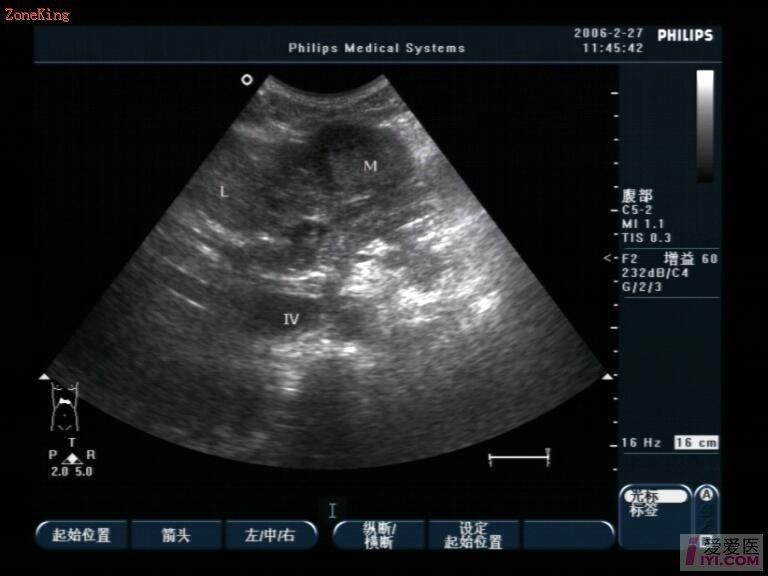

肝脏:右叶斜径约125mm,包膜欠光滑,肝静脉清晰,实质回声欠均质,肝左叶探及约42mm×35mm中等偏低回声,边界尚清,边缘欠规则,其内回声欠均匀,CDFI:包块内及周边加彩填色可见少许树枝状彩色血流信号,PW:其中一支动脉:RI:0.88,PSV:32.4cm/s;门静脉内径13 mm,出肝门大量气体干扰显示欠清。

肝左叶探及约42mm×35mm中等偏低回声,牵拉包膜,引起腹痛,回声不均质,并且RI:0.88,PSV:32.4cm/s;占位改变最大,门静脉内径13 mm,不算很宽,正常可以考虑1.4CM,作为参考值,内部回声不是很清楚。符合肝实质内占位性超声改变